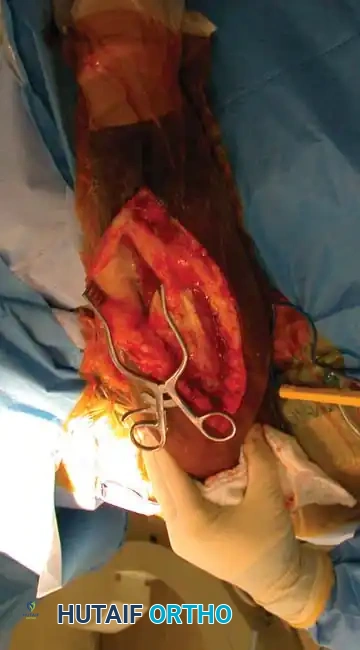

5. Deep Dissection and Radial Nerve Mobilization:

* Elevate the lateral head of the triceps off the lateral intermuscular septum.

* Identify the radial nerve and the profunda brachii artery as they pierce the lateral intermuscular septum to enter the anterior compartment.

* Carefully mobilize the radial nerve. Use vessel loops for gentle retraction. Never apply excessive traction to the nerve.

Fig. 54-33 D, Mobilization of the radial nerve.

6. Fracture Reduction and Fixation:

* Reflect the entire triceps muscle mass medially to expose the posterior humeral shaft.

* Reduce the fracture and apply the pre-selected LC-DCP. Ensure the radial nerve is completely free and not tethered beneath the plate.